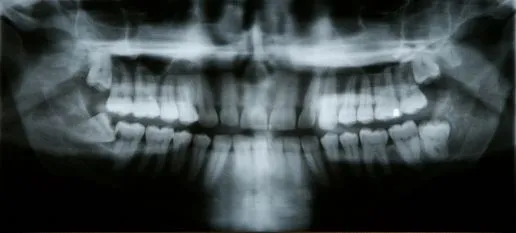

After Impacted Tooth

A tooth becomes impacted when there is not enough room to accommodate the space in the dental arch and growth becomes impossible.  After surgery to remove an impacted tooth, mild discomfort and some swelling is expected. This is part of the process and should not alarm you. You may use cold compresses to alleviate the swelling. In addition, your doctor will prescribe pain medication, which should be taken as directed. Patients are also advised to favor the extraction area and modify their diet for a few days to allow for healing.